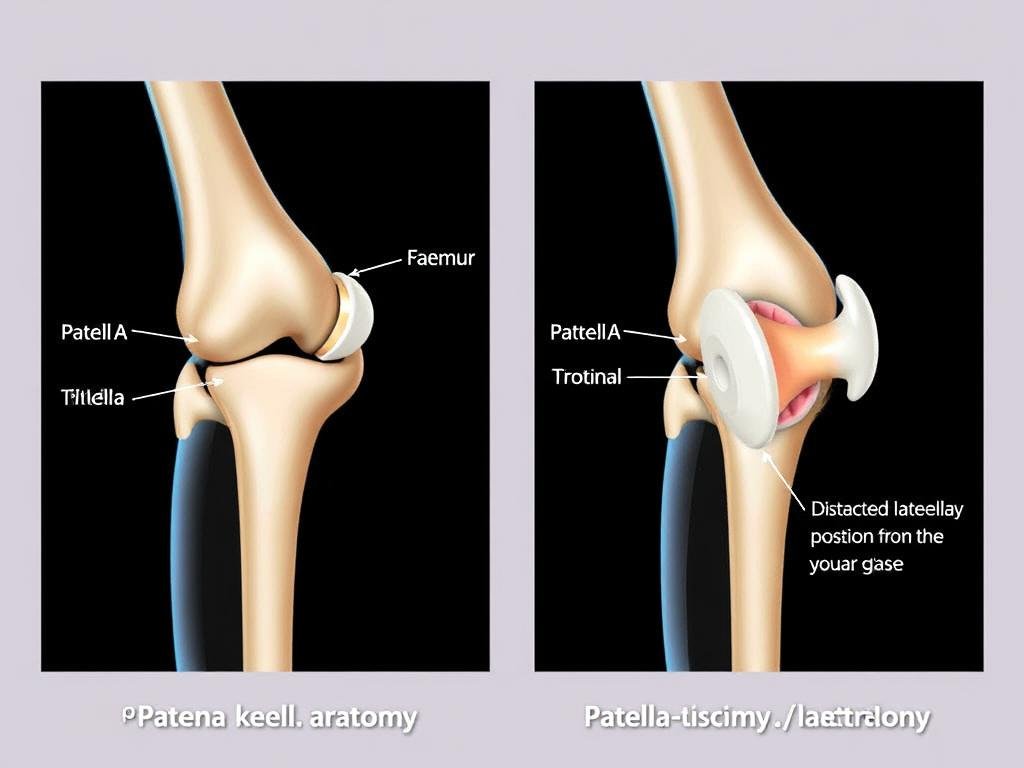

Typisches Erscheinungsbild einer Patellaluxation mit sichtbarer Fehlstellung der Kniescheibe und Schwellung